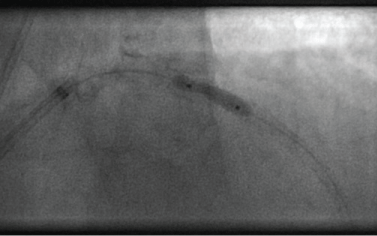

Shortly thereafter, a second case of shaft rupture of an ultra-high pressure balloon occurred in our catheterization laboratory at the Helios Albert-Schweitzer-Hospital, Northeim, Germany. This patient presented in May 2015 with a non ST-elevation acute coronary syndrome with troponin elevation. Coronary angiography showed 3-vessel disease with a 90% stenosis in the RCA. Our strong recommendation to undergo urgent surgical bypass grafting was vehemently and repeatedly rejected by the patient. Therefore, PCI of the culprit lesion in the distal RCA was attempted. As a 2.5 mm non-compliant balloon catheter still displayed significant "dog-boning" in the calcified lesion at 26 atms (Figure 6), ultra-high pressure angioplasty was performed with a 2.5 mm OPN balloon. Rupture occurred at an inflation pressure of 36 atm, just above "rated burst pressure". Again, it was not the balloon itself that teared open but the distal catheter shaft (Figure 7). In this second case however, the distal part remained attached to the catheter shaft, contrast medium drained retrogradely into the ascending aorta and removal of the partially inflated balloon could be safely performed without complications.

Figure 6: "Dog-boning" of ultra-high pressure balloon in RCA at 35 atm in patient 2. View Figure 6